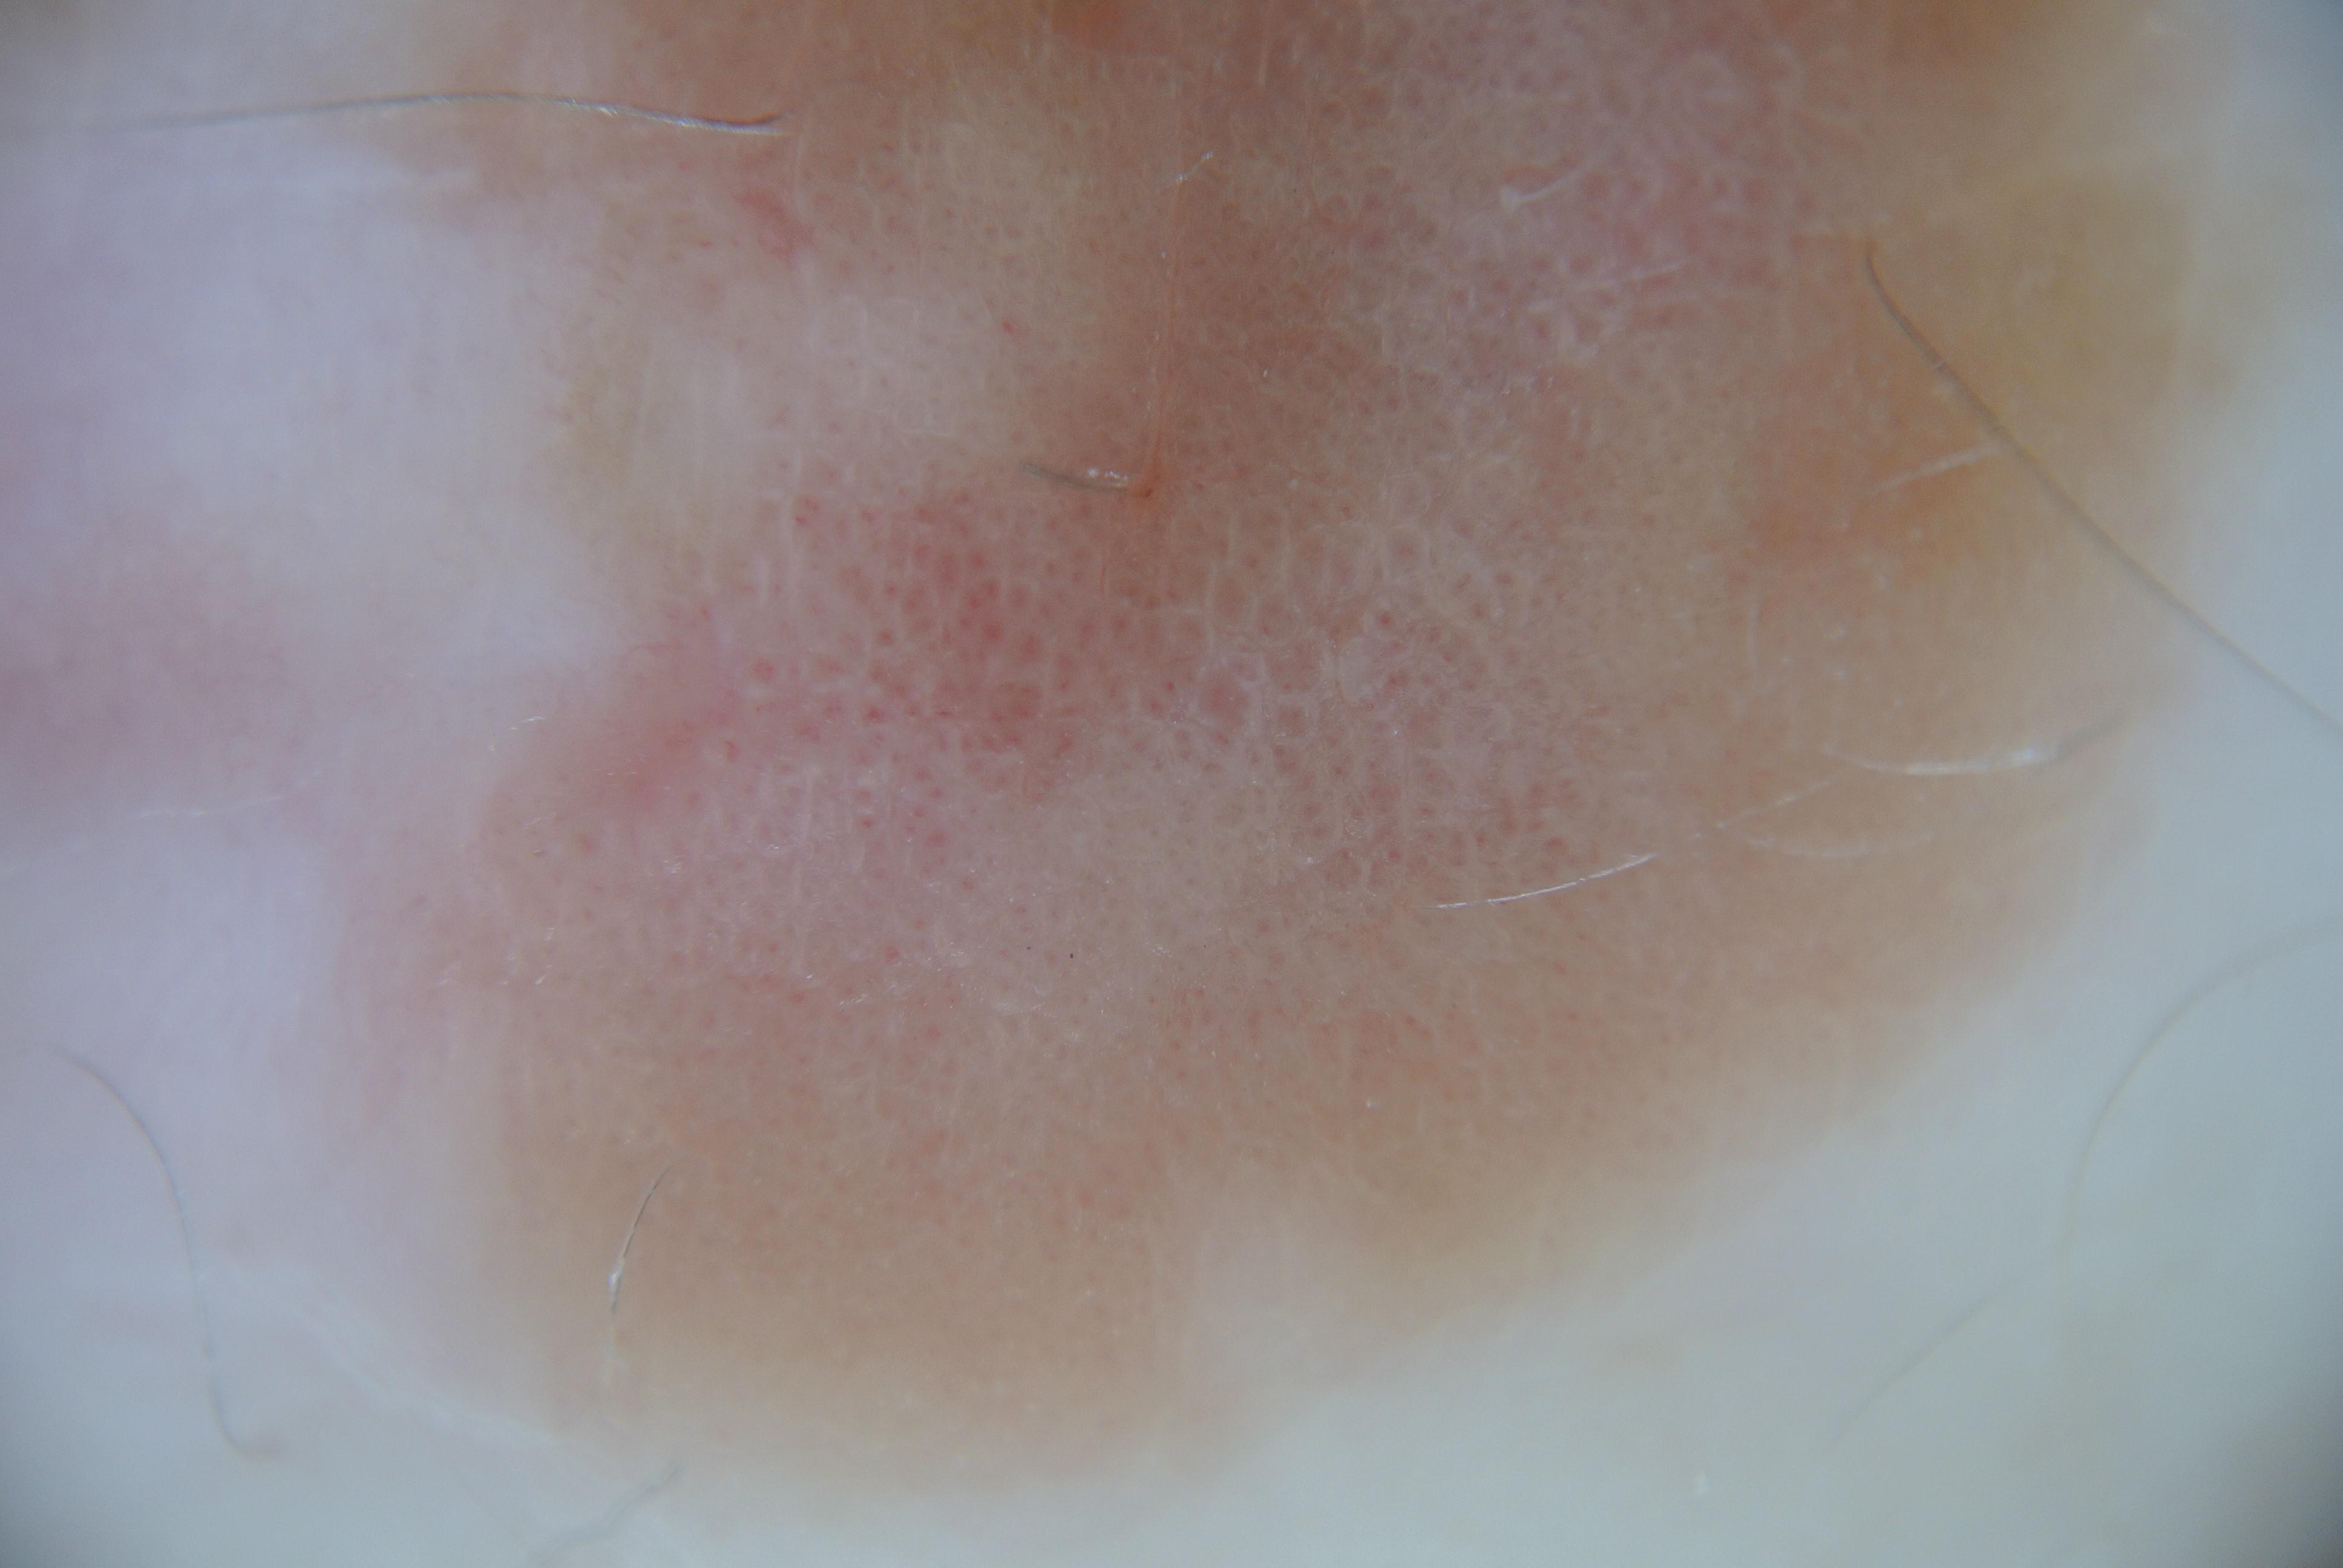

{

"age_approx": 65,

"anatom_site_general": "anterior torso",

"concomitant_biopsy": true,

"dermoscopic_type": "contact non-polarized",

"diagnosis_1": "Malignant",

"diagnosis_2": "Malignant melanocytic proliferations (Melanoma)",

"diagnosis_3": "Melanoma in situ",

"diagnosis_confirm_type": "histopathology",

"family_hx_mm": false,

"image_type": "dermoscopic",

"mel_thick_mm": "0.00",

"melanocytic": true,

"patient_id": "IP_4465811",

"personal_hx_mm": true,

"sex": "male"

}